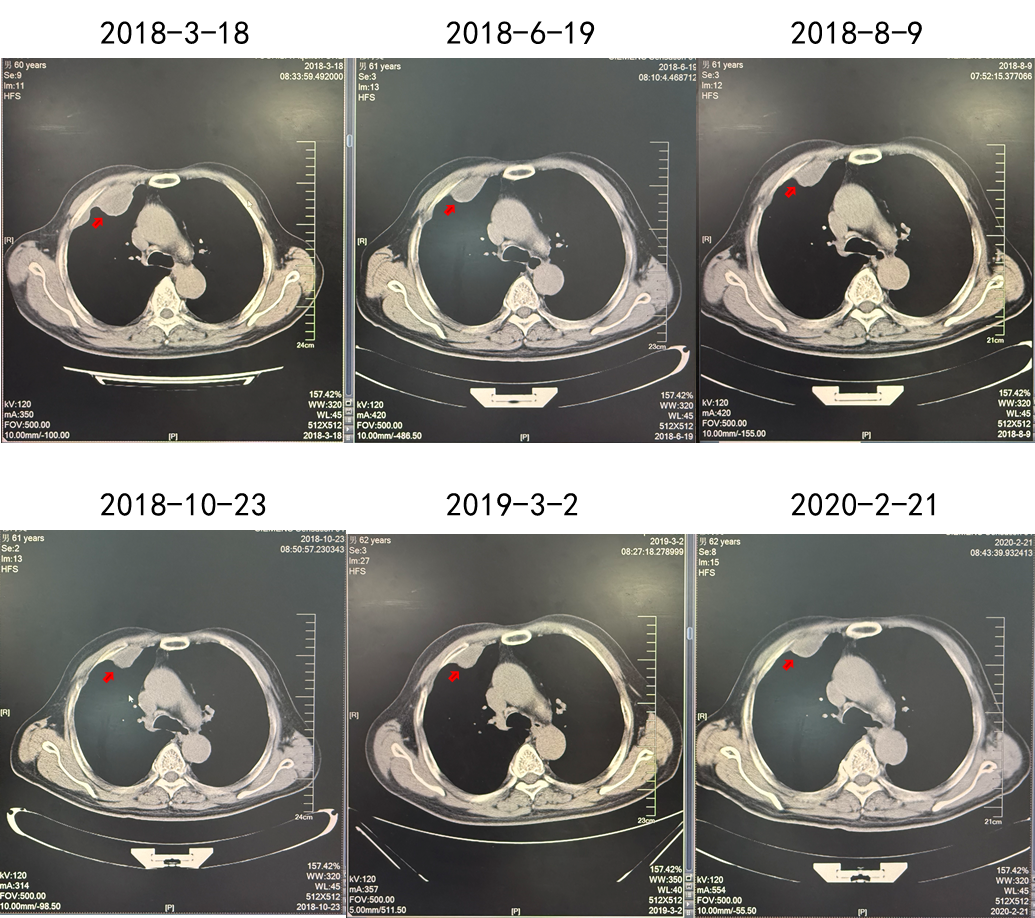

第二阶段:靶向治疗同步放疗

2018.03.22舒尼替尼50 mg QD。肋骨肿瘤注射唑来膦酸3周1次(共3次),同步放疗3 Gy(共10次)。

2018.03.24由于患者出现不良反应,调整剂量为37.5 mg QD。

疗效:肋骨病灶疾病稳定(2年),肺部病灶部分缓解(2年)。

(舒尼替尼单药联合放疗,肋骨病灶实现SD)

(舒尼替尼单药联合放疗,肺转移病灶实现PR)

(治疗停滞1年,患者对侧肾上腺肿瘤发生进展)